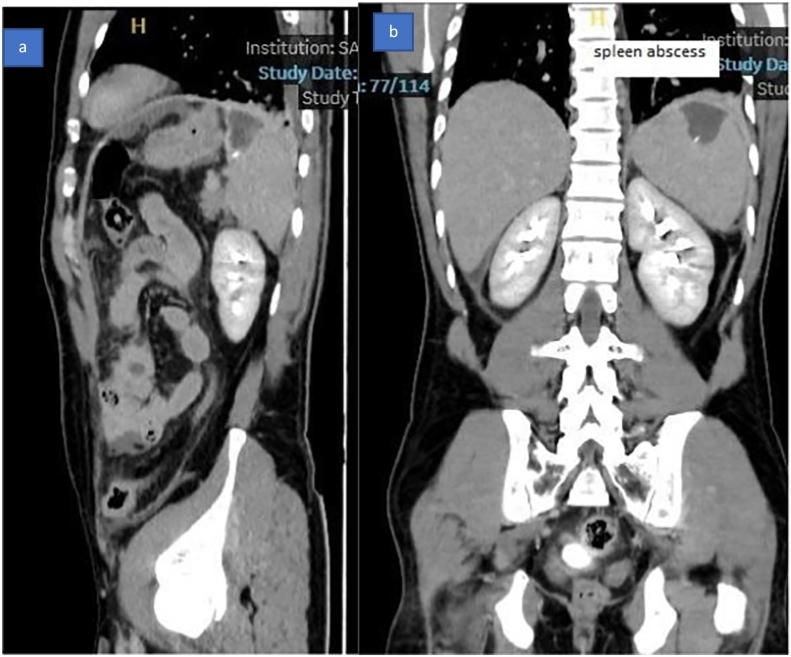

We report a case of fishbone penetration from the stomach into the spleen, presenting as a splenic abscess and acute peritonitis, diagnosed pre-operatively with a contrast-enhanced CT scan of the abdomen and subsequently managed with spleen-preserving surgery.

A rare case of fishbone penetration from the stomach into the spleen causing a splenic abscess was diagnosed radiologically pre-operatively and managed by a spleen-preserving procedure.